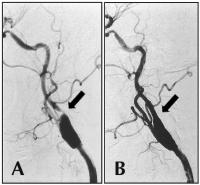

Abbildung 2: Höchstgradige Abgangsstenose der A. carotis interna rechts; A) vor Stentangioplastie; B) nach erfolgreicher Stentangioplastie